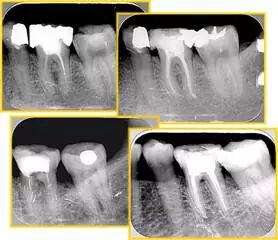

( 1 )干髓。

干髓治疗时,开髓后髓腔里注入甲醛甲酚 FC 灌髓,三聚甲醛固定,髓室底放置三聚甲醛缓慢释放,进行根管无害化处理。髓腔缓慢坏死,机体代偿出现根管钙化。如果患者在封闭腔出现出现病变,由于髓腔钙化,根管堵塞严重,检查治疗比较困难。

解决方法:1 )彻底去除坏死的牙髓组织。2 )借助化学性药剂,如 EDTA 等。3 )初锉选用8#或10#K 锉,平衡力法探察到工作长度 , H锉上下提拉法使根管扩大,提高工作效率。

牙胶尖什么颜色​牙齿“晓”“技”|最全根管治疗的标准步骤,以及细节把握_https://www.jmylbn.com_新闻资讯_第22张

左图和上图为干髓治疗后牙齿,龋齿疏通后进行根管充填。